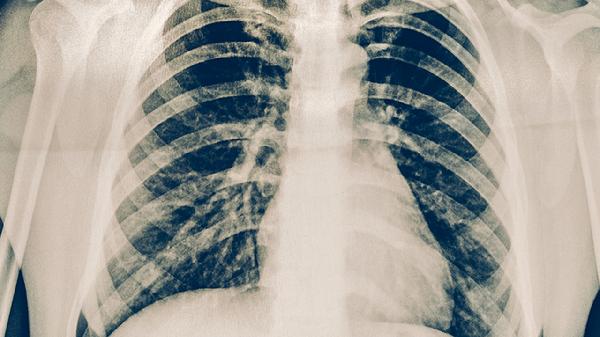

肺力咳合剂具有清热化痰、止咳平喘的功效,主要用于治疗痰热壅肺引起的咳嗽、气喘、痰黄黏稠等症状。该中成药的主要成分包括黄芩、前胡、百部、桑白皮、紫苏子等,具有抗炎、抗菌、祛痰、舒张支气管的作用。